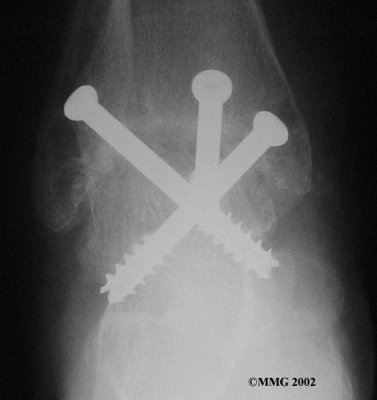

It is important when the surfaces are removed that the angles of the cut surfaces are correct. When the tibia is brought against the talus, the foot should be at a right angle to the lower leg. Once the cuts are made the bones must be held in place while they fuse. This can be done using large metal screws and metal plates if necessary. The screws are usually under the skin and are not removed unless they begin to rub and cause pain.

Inserting the screws

After ankle fusion, the physical therapists at FYZICAL Therapy & Balance Centers - Roswell can help you learn to walk smoothly and without a limp. Although time needed for recovery varies among patients, an ankle brace will typically replace your cast after eight to 12 weeks. Your surgeon will take X-rays frequently to see if the bones are fusing together. You will probably need to use crutches during the time you wear the cast. As the fusion grows stronger, you will begin to put more weight on your foot when walking.